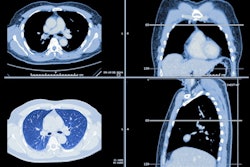

The initial findings show the feasibility of using Tc-99m maraciclatide to evaluate disease activity. The findings are part of a sub-study of the PRospective Evaluation of Interstitial Lung Disease progression with quantitative CT (PREDICT-ILD) phase II clinical trial.

The university is leading research efforts, with the sub-study including 10 patients and five healthy controls. The findings include increased activity in patients with interstitial lung disease compared to healthy controls and feasible visualization of inflammation in patients. The researchers also found that whole lung uptake of the imaging marker was greatest in those with fibrotic hypersensitivity pneumonitis.